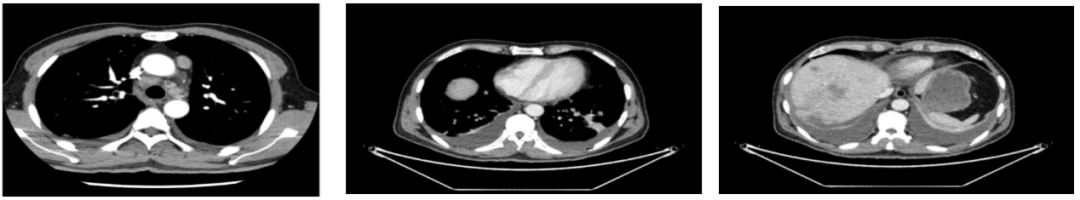

外院CT检查提示:1、两肺多发斑片状、结节影,性质待定,转移瘤?2、纵隔内多发肿大淋巴结;3、肝实质多发稍低密度影,性质待定(转移瘤可能性大)

2018-03-08 PET/CT示:胃癌(?)并全身多发淋巴结转移、肝脏多发转移、双肺上叶多发转移;

2018-11-14 CT(8周期化疗后):PD?

胃壁代谢稍增高但未见明确的肿物,肝内低代谢结节考虑转移瘤治疗后活性减低,纵膈及右肺门两个淋巴结代谢增高,考虑转移瘤活性尚存、左侧颞骨局部骨质破坏并代谢增高,考虑转移瘤。

经科内讨论,建议患者继续原方案SOX+赫赛汀化疗,左侧颞顶交界区骨质破坏局部射波刀治疗。